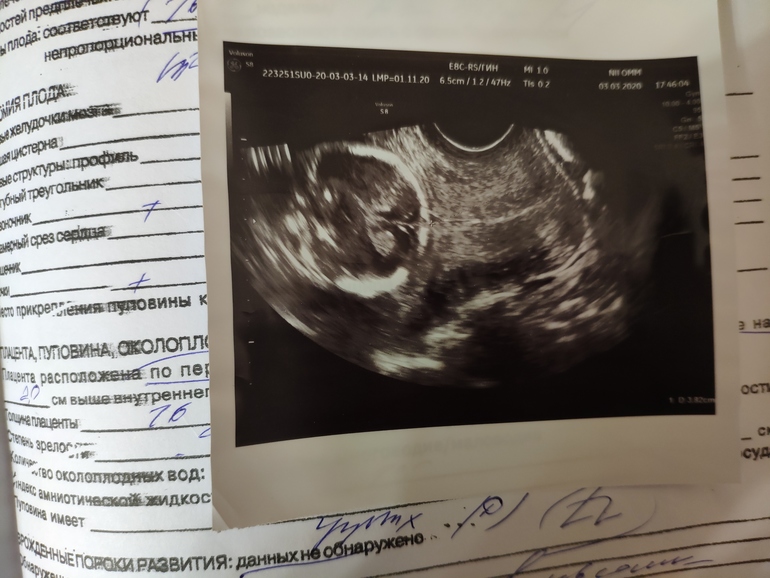

УЗИ, КТГ, доплерПрикладываю фото. Я так понимаю, что это ножки? Как бы вид снизу вверх?) Срок тут 16 недель.

Это головка и шейка матки.

Иными словами кадр с цервикометрии.

Там по моему снизу 3.8 написано. Значит шейка 38 мм

По мне так классический ракурс для определения пола - попа и ноги, на фото девочка